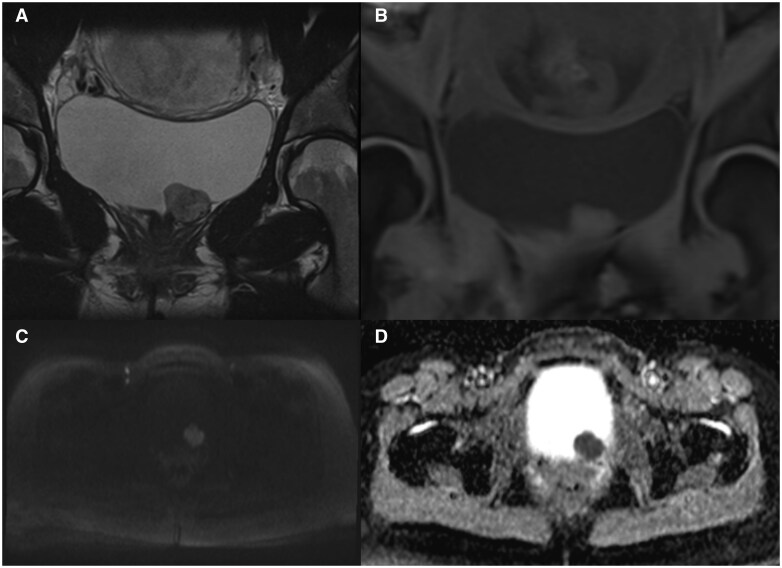

Paragangliomas (PGLs) during pregnancy is an uncommon neuroendocrine tumour that is associated with increased maternal and foetal morbidity and mortality. Furthermore, it is even rarer for these to be located within the urinary bladder, with a prevalence of <0.1% of all bladder tumours. This case report details a 29-year-old female who presented with pre-syncope, headache, and palpitations during voiding. Ultrasound and magnetic resonance imaging of the pelvis revealed a mass in her bladder, and biochemical workup demonstrated elevated plasma normetanephrine levels and a positive clonidine suppression test. Surgical resection and histopathology of the mass were consistent with PGL. Post-operatively, the patient was normotensive, her normetadrenaline levels normalized and she was discharged 3 days after the operation. She progressed through the remaining pregnancy without any significant complications and delivered a healthy baby at full term. This case depicts the rare nature of PGLs in pregnancy and the importance of antenatal imaging combined with a multidisciplinary approach for a successful pregnancy outcome.

Abstract Image